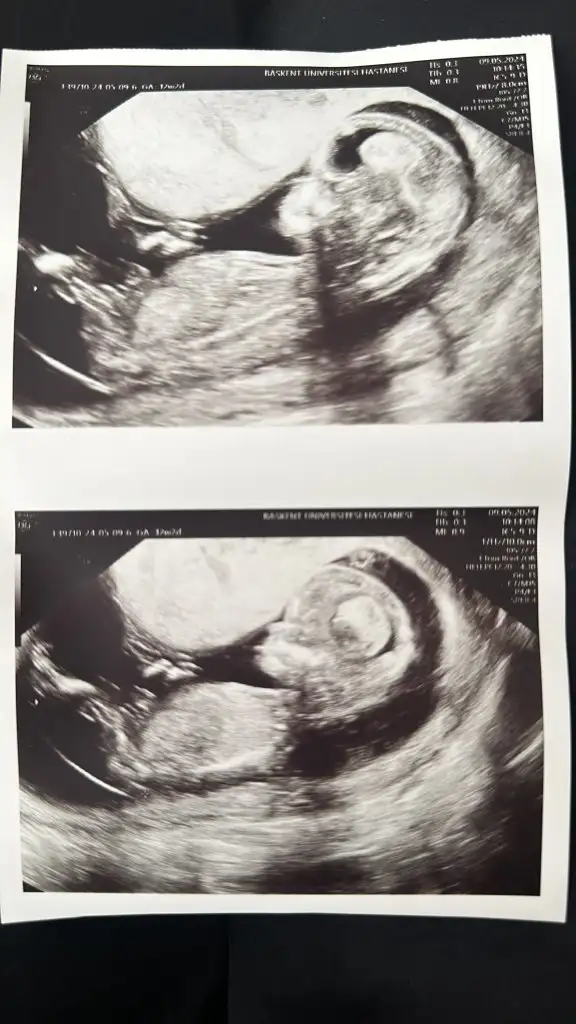

Canım kız gibiBanada bakarmisiniz 12 haftalik pek kıpırdamadan ama merak ediyorumEki Görüntüle 3420926 Eki Görüntüle 3420927 Eki Görüntüle 3420928

Canım erkek gibiBenimkinede bakarmısınız 12+2 haftalık ben kız olduğunu düşünüyorum ama bilemedim

Bir çıkıntı var ama anlayamadım görüntünüz aslında çok net.Benimkinede bakarmısınız 12+2 haftalık ben kız olduğunu düşünüyorum ama bilemedim